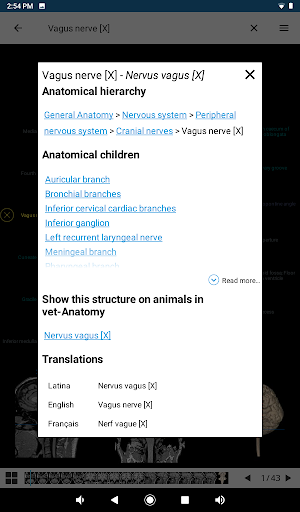

* التفاعلات الثابتة مع التسلسل الهرمي التشريحي

* تصفح بين الأجزاء التشريحية باستخدام روابط الوصف